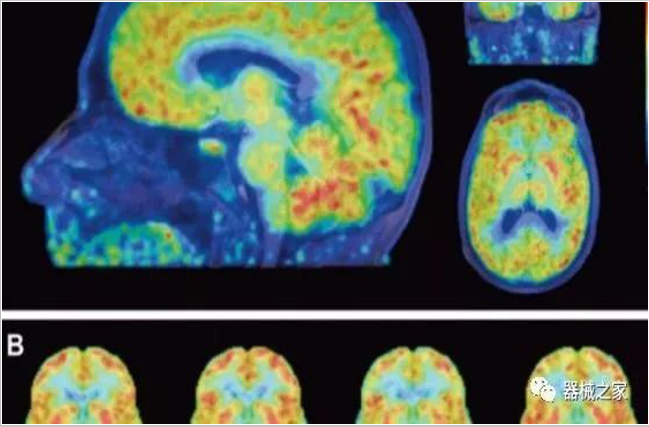

正電子發(fā)射型斷層儀(Positron Emission Tomography, PET)是對正電子示蹤劑的探測設備,具有極高靈敏度和精準的定量功能。而PET/CT是將PET與CT有機結合起來的融合設備,已經成為腫瘤、神經和心血管系統(tǒng)疾病診斷,臨床分期和療效評估的最佳影像技術。